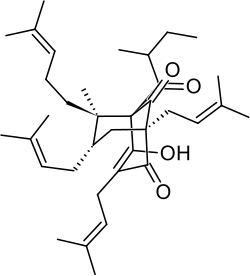

Chemistry

Hyperforin is a prenylated phloroglucinol derivative and is a member of the Polycyclic polyprenylated acylphloroglucinol family, also known as the PPAP family. Hyperforin is a unique PPAP because it consists of a C8 quaternary stereocenter which was a synthetic challenge unlike other PPAP synthetic targets.[3][4][10] The structure of hyperforin was elucidated by a research group from the Shemyakin Institute of Bio-organic Chemistry (USSR Academy of Sciences in Moscow) and published in 1975.[11][12] A total synthesis of the non-natural hyperforin enantiomer was reported in 2010 which required approximately 50 synthetic transformations.[13] In 2010, an enantioselective total synthesis of the correct enantiomer was disclosed. The retrosynthetic analysis was inspired by hyperforin's structural symmetry and biosynthetic pathway. The synthetic route undertaken generated a prostereogenic intermediate which then established the synthetically challenging C8 stereocenter and facilitated the stereochemical outcomes for the remainder of the synthesis.[10]

Hyperforin is unstable in the presence of light and oxygen.[14] Frequent oxidized forms contain a C3 to C9 hemiketal/heterocyclic bridge or will form furan/pyran derivatives.[7][8]

- Natural and semi-synthetic analogues of Hyperforin

-

-

Aristoforin

Aristoforin -

Hyperforin trimethoxybenzoate

Hyperforin trimethoxybenzoate -

Tetrahydrohyperforin

Tetrahydrohyperforin -

Hyperforin nicotinate

Hyperforin nicotinate